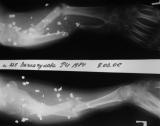

Огнестрельный дефект предплечья

Уважаемые коллеги! Хотелось бы услышать Ваше мнение по лечению больной 22 лет. Травма год назад - огнестрельное ранение. Лечилась в ЦРБ - хирургическая обработка и фиксация предплечья в аппарате Илизарова - фиксационный вариант. Впевые обратилась к нам в сентябре 2005г.

На рентгенограммах приведены картинки - одна без вмешательств, другая в условиях ручной тракции по оси предплечья. Кисть была полностью нефункциональна - сгибательные контрактуры всех пальцев, выраженный отек кисти, Было решено, что тактику лечения определим после попытки восстановления функции кисти. На сегодня - полное восстановоение объема движений в пальцах за исключением активного отведения 1 пальца. Больная даже вяжет на спицах. Больная не очень дисциплинирована, выписывалась из стационара за алкогольные радости, длительное лечение с использованием ЧКДОС мало реально.